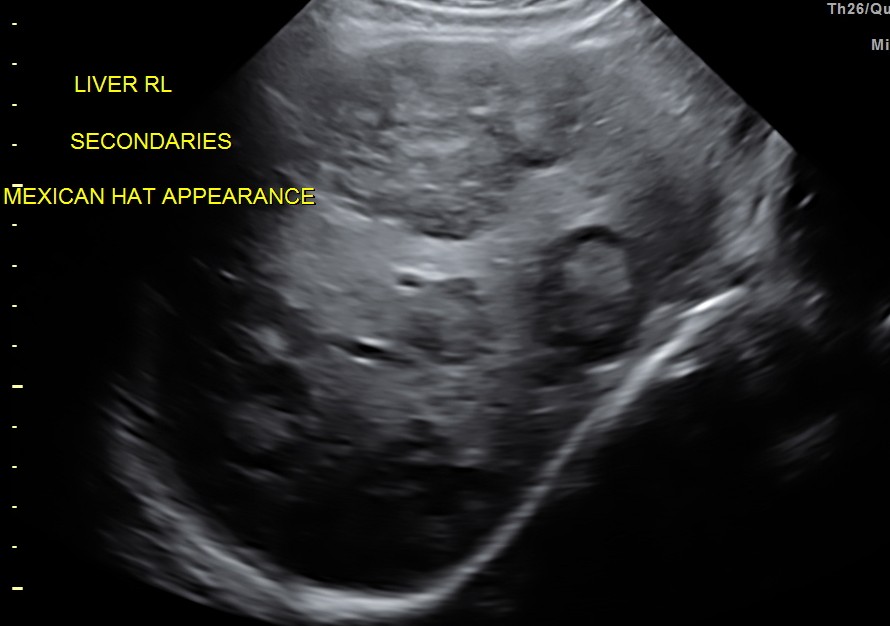

His liver showed multiple secondaries .

secondaries show target appearance or bird’s eye view of mexican hat appearance

DISCUSSION : Generally the target sign or the bird’s eye view of the Mexican hat sign could signify colo-rectal carcinoma.